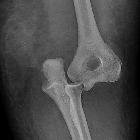

Plain radiograph

The dislocation is usually obvious, especially if adequate AP and lateral views are obtained, however, the challenge is in identifying associated fractures.

- associated fractures

- most frequently the radial head and coronoid process

- other fractures encountered include medial epicondyle (in children), lateral condyle, capitellum, olecranon